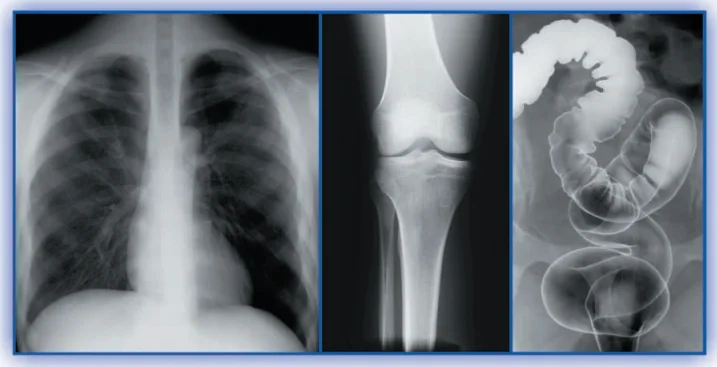

It is a kind of traditional conventional medical x-ray film, used for the examination of human body disease and abnormal changes of viscera, bones and soft tissues, providing reliable information for clinical diagnosis.